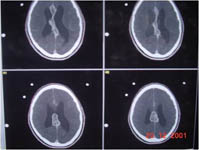

Radiosurgery Gallery